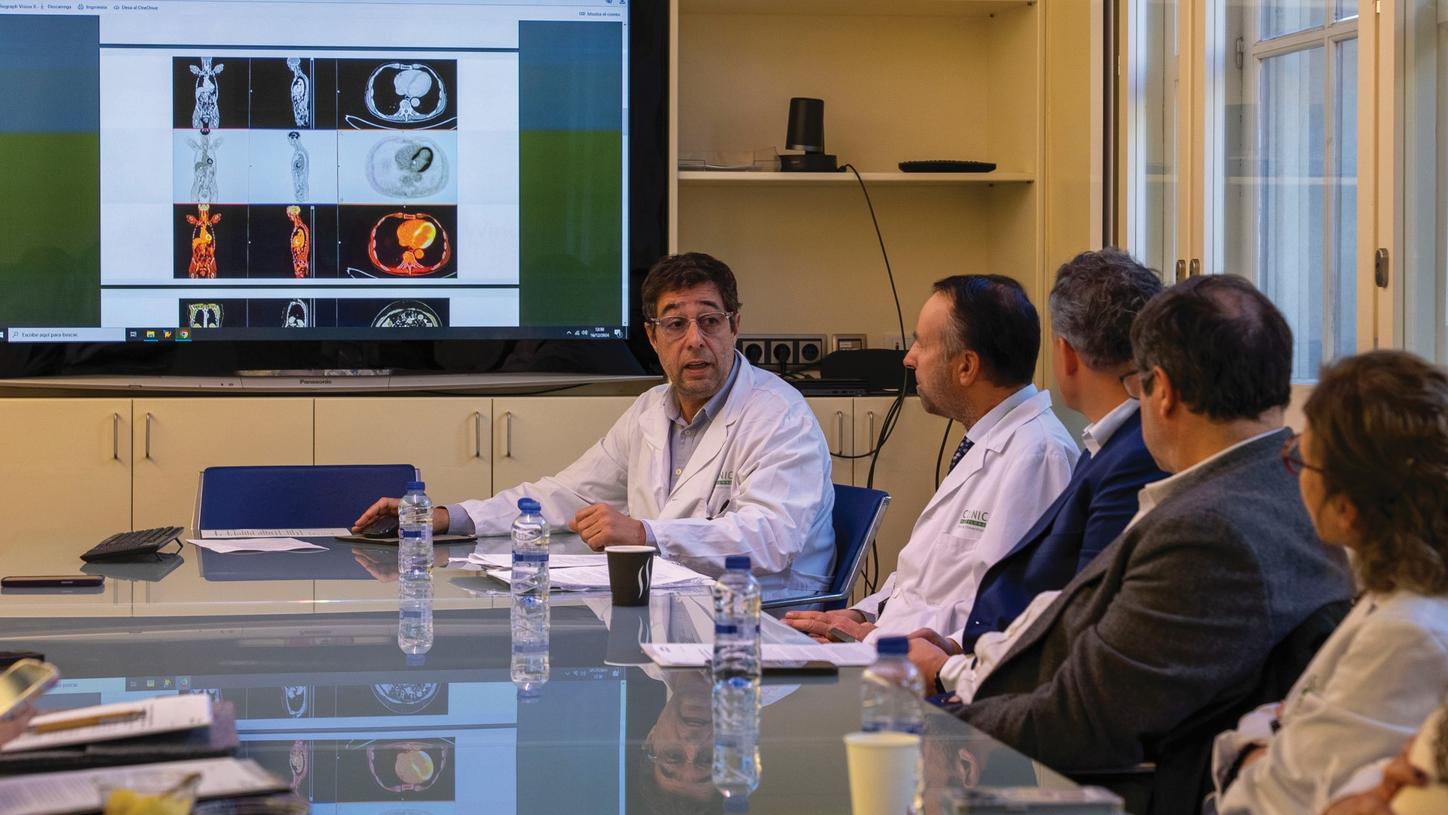

Answering to clinical needs in oncology, neurology, cardiology, and radiology, Siemens Healthineers Molecular Imaging systems provide PET/CT, SPECT, and hybrid SPECT scanner (SPECT/CT) solutions to help clinicians diagnose, treat, and monitor diseases more confidently.